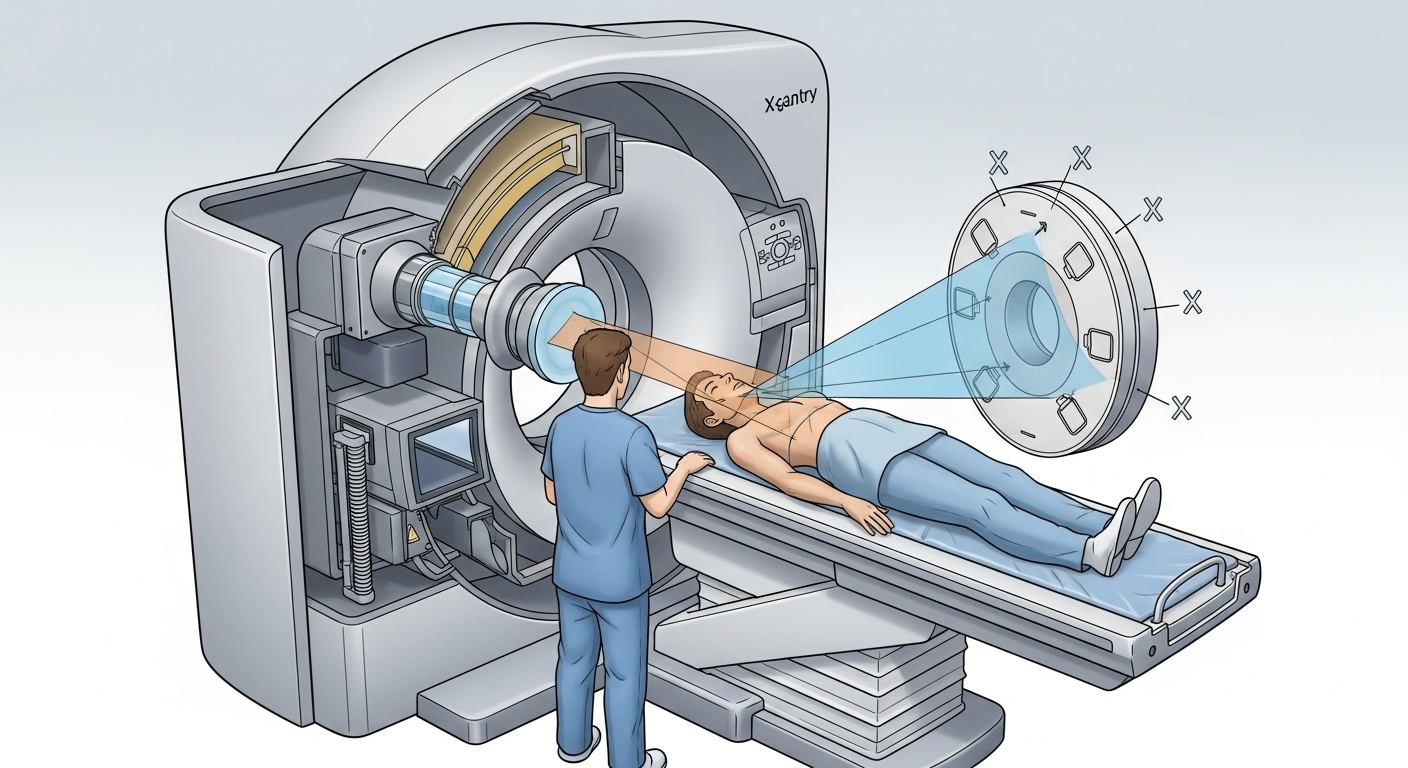

Embora o processo de uma tomografia seja tecnicamente complexo, podemos simplificá-lo em etapas lógicas para facilitar a compreensão. Veja como os dados são transformados em diagnósticos:

1. A Emissão Controlada de Raios-X

O primeiro passo envolve a emissão de feixes de raios-X através do corpo do paciente. No entanto, o diferencial aqui é que o tubo de raios-X gira em torno da pessoa dentro de uma estrutura circular chamada gantry.

2. A Captura pelos Detectores

Do outro lado do paciente, existe um conjunto de detectores digitais de alta sensibilidade. Enquanto o tubo gira, esses detectores registram continuamente a quantidade de radiação que emerge do corpo. Cada sinal captado representa uma “perspectiva” diferente da estrutura interna, gerando milhares de pontos de dados em poucos segundos.